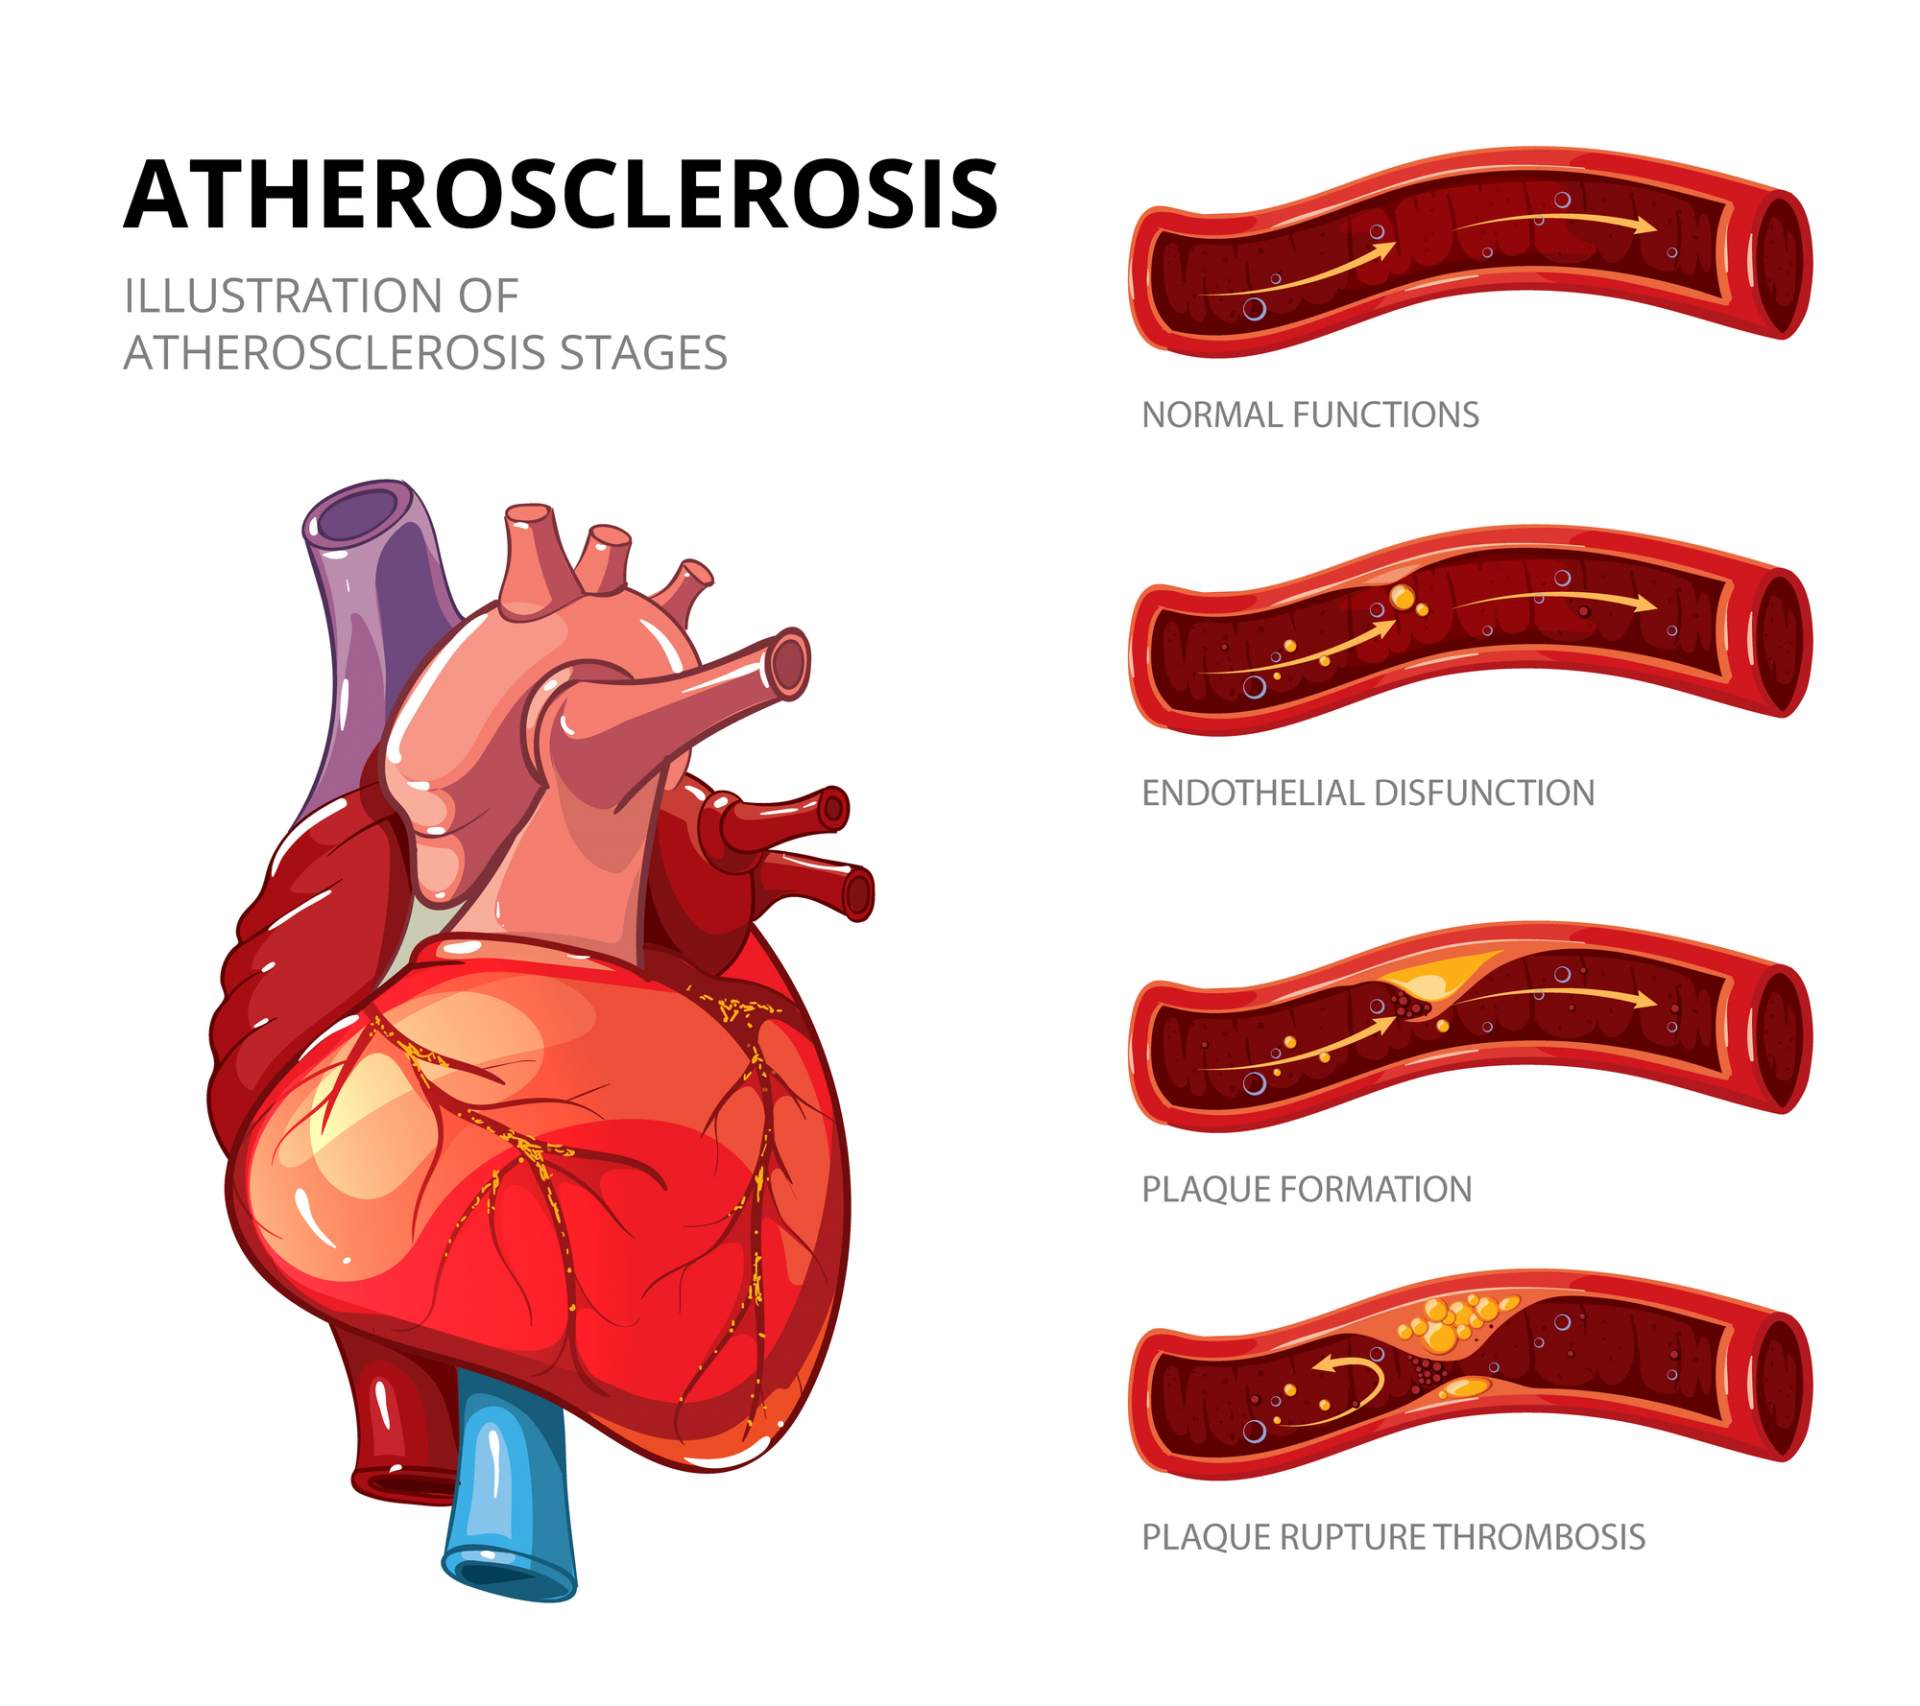

Atherosclerosis stages. Normal functions, endothelia disfunction …

Stages of atherosclerosis Stock Vector Image by ©edesignua #144301487

Atherosclerosis Stages: Healthy Artery, Plaque Formation, and …